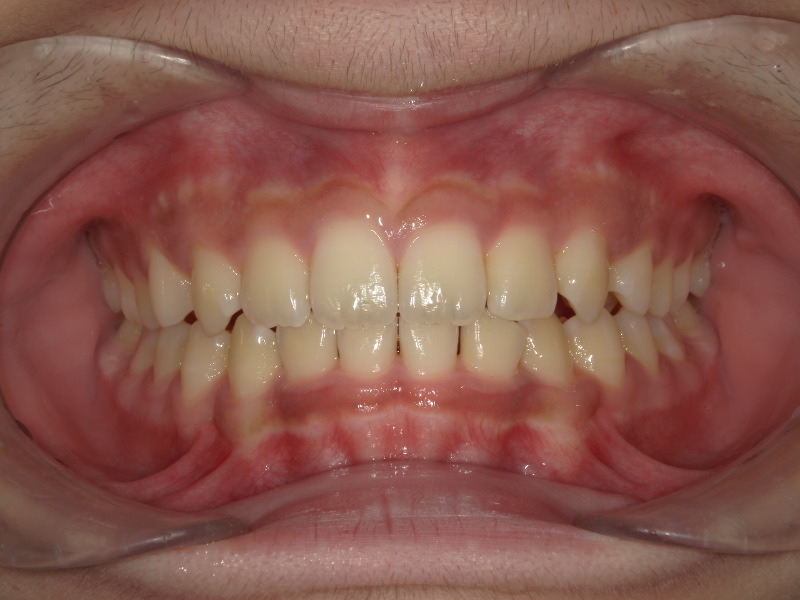

噛み合わせの変化

一年半頃の写真です。

しっかり下の歯が見えてきています。

噛み合わせが深かったのが前にくる=下顎は前に成長しています。

そのため、顎の位置変化が起き、下の顎のアーチは大きくなり、がたつきも改善していきます。